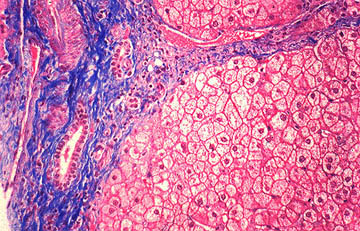

li-11-9-3.jpg (55040 bytes)Fig. 11-10-3. Advanced chronic stage.

Intralobularly there may be heavy bile lakes and presence of foamy histiocytes (xanthomatous cells). Periportal fibrosis develops with proliferation of bile ductules surrounded by fibrosis at the periphery of the portal field.